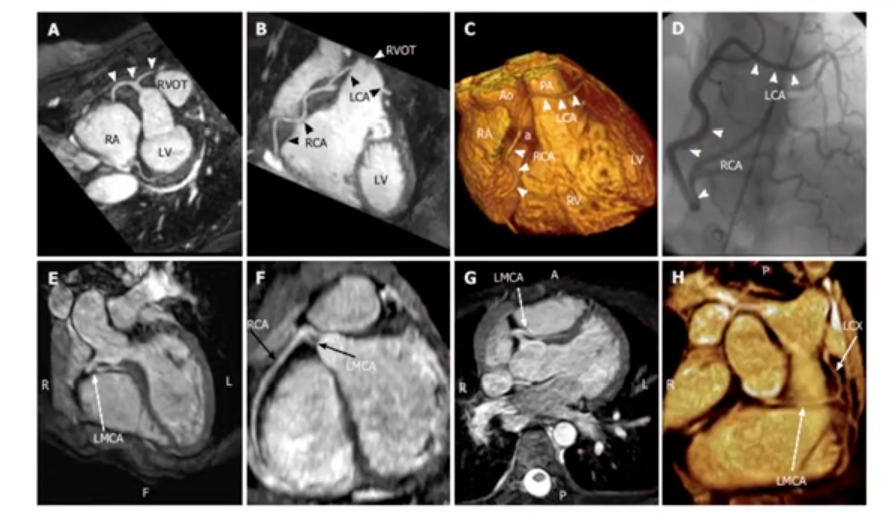

▌冠状动脉起源异常

右冠高位起源:

图7

牧羊鞭样冠脉:

图8

右冠起源于前降支:

图9

LCX起源右窦:

图10

LAD起源右窦:

图11

单一的冠脉:

图12